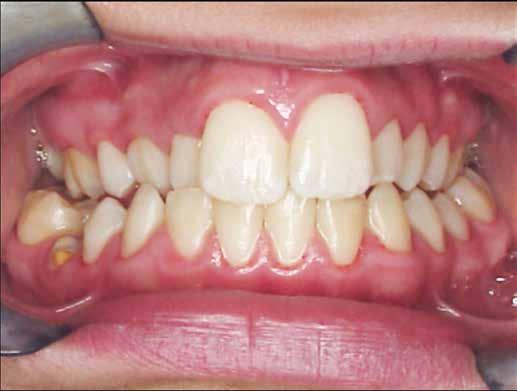

A kezelés befejezésekor a páciens mosolya drámai mértékben javult, továbbá a frontfogak elhelyezkedése és az ínyszél lefutása is szemmel látható módon kedvezőbbé vált (4. ábra). A kezelés végén készült CBCT felvétel nem mutatta

4. b ábra: A panoráma röntgenfelvétel is alátámasztja a CBCT felvételen látottakat. 4. c ábra: Az intraorális felvételen megfelelő fogpozíciók és kedvező ínyszéli lefutás ábrázolódik.